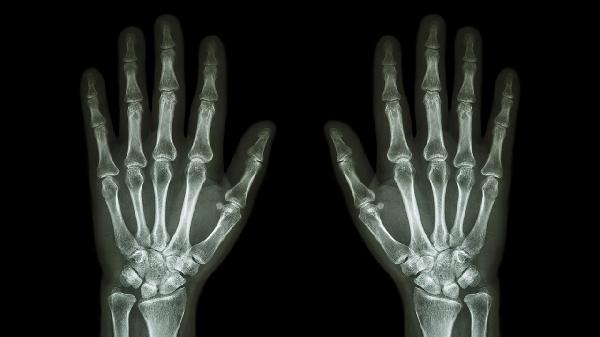

类风湿关节炎可能与自身免疫异常、遗传等因素有关,通常表现为对称性关节肿胀、畸形等症状。患者可遵医嘱使用甲氨蝶呤片、来氟米特片、艾拉莫德片等药物控制病情。建议定期复查类风湿因子和关节X线检查。